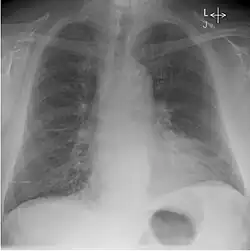

Kerley-Linien sind zarte Linien auf dem Röntgenbild der Lunge. Sie weisen auf pathologisch verbreiterte Alveolarsepten und Lymphgefäße der Lunge hin, am häufigsten verursacht durch eine Herzinsuffizienz. Auch Pneumonien, Lungenfibrose und eine diffuse Absiedlung von Tumorzellen in der Lunge (Lymphangiosis carcinomatosa) können zu sichtbaren Kerley-Linien führen.

Unterschieden wird zwischen feinen, langen Kerley-A-Linien eher in den oberen Lungenabschnitten und kurzen, waagerechten Kerley-B-Linien, die in den unteren Lungenabschnitten nahe der Thoraxwand im so genannten costophrenischen Winkel verlaufen (vorwiegend rechtsseitig). Kerley-C-Linien sind spinnwebenartige Linien über der gesamten Lunge.